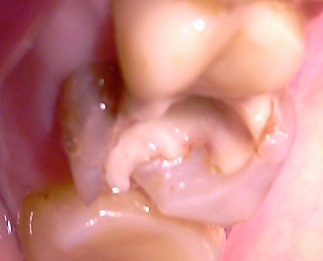

Вот, что мы видим, убрав пломбы с зуба.

Обширный кариозный процесс.

Кстати, вторая пломба на этот зуб была поставлена 3 года назад, уже имея кариес под первой пломбой (как оказалось после того, как были убраны старые пломбы).

В доказательство, кариозные процессы разделены здоровой тканью.

К счастью, вмешались мы вовремя и нерв удалять не пришлось, зато удалили большое количество кариозной ткани. В результате этого приняли совместно с пациенткой решение ставить керамическую вкладку.